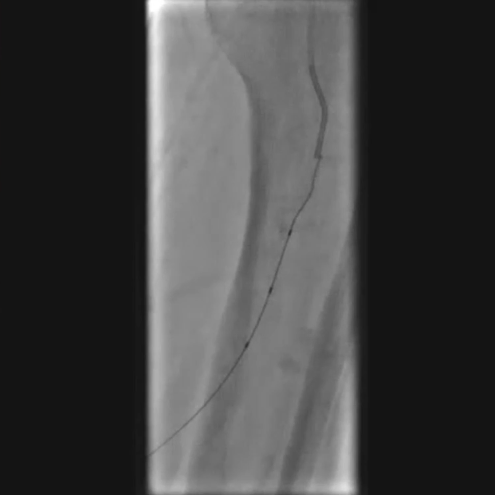

铁基可降解支架植入

按计划植入3×38mm载药铁基可降解支架,准确定位以完全覆盖病变;采用8 atm压力球囊扩张释放支架,确保支架充分张开。